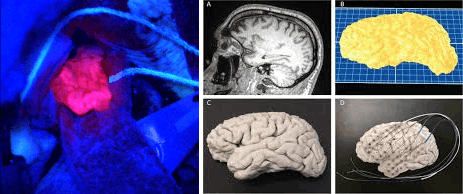

На рубеже 19–20 веков нейрохирурги удаляли только крупные и поверхностные образования мозга — опухоли, гематомы, фрагменты долей больших полушарий. Для планирования операции они использовали анатомические атласы, о которых мы говорили выше, для доступа к мозгу проводили трепанацию (создавали отверстие в черепе под наркозом, формируя костный лоскут в виде «крышки») (рис. 22А), если требовалось определить границы жизнеспособных тканей в этой области — будили пациента во время операции и просили его выполнять задания или стимулировали его мозговую ткань электродами, чтобы не вырезать лишнего.

Традиционная нейрохирургия продолжает развиваться (рис. 22Г): используются операционные микроскопы, снимки МРТ/КТ показывают необходимое место и объем операции. Появились методы, позволяющие лучше ориентироваться в оперативном поле: флуоресцентная навигация, когда опухолевая ткань начинает «светиться» на фоне здоровой; 3D-навигация, учитывающая положение инструмента относительно тканей на основе инфракрасных датчиков и данных МРТ. Если раньше нейрохирурги отрабатывали оперативный доступ на мозгах животных, то теперь на основе индивидуальных МРТ-снимков и 3D-принтера они воссоздают точную 3D-копию черепа и мозга пациента, чтобы подготовиться к операции.